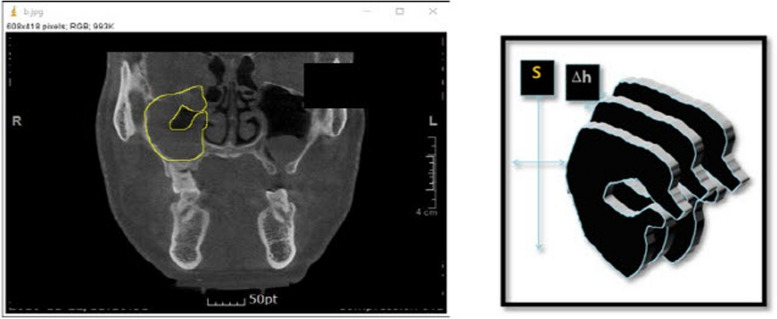

Background: Odontogenic maxillary sinusitis (OMS) is widely acknowledged in both the dentistry and otolaryngology fields. Recently, iatrogenic odontogenic maxillary sinusitis cases can be encountered frequently. The purpose of this study was to evaluate the effect of intraoral sinus irrigation using the small lateral window approach in patients with odontogenic maxillary sinusitis by comparing pre- and postoperative volumetric measurement of CBCT and symptoms. We surveyed 21 patients who visited the Oral and Maxillofacial Surgery Department at PNUDH from 2016 to 2022. All the patients' information was extracted from an electronic database. The patients with a follow-up period of 2 months or more were included. The three-dimensional volumetric measurement was performed using the ImageJ program (National Institute of Health, University of Wisconsin).

Results: Among 21 patients, 16 (76.1%) were male, and 5 (23%) were female. The most common type of surgery was general anesthesia (16 cases) in which oroantral fistula was present in 7 cases. In the causes of maxillary sinusitis, there were seven implant-related patients, five patients of tooth extraction, seven patients of bone grafting, and two patients in other groups. Radiographic opacity decreased by 40.15% after sinus irrigation especially in bone graft and tooth extraction cases. Clinically, symptoms improved in 17 patients (80.9%).

Conclusion: By this study, it can be concluded that maxillary sinus irrigation using the small lateral window approach is a clinically and radiologically effective treatment method for odontogenic maxillary sinusitis.